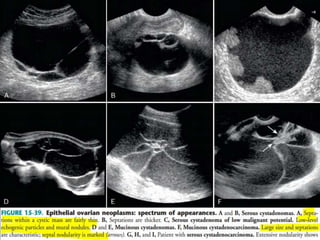

This document contains an image gallery from Dr. Mohit Goel showing various uterine anomalies and ovarian cysts. It includes images of an arcuate and unicornuate uterus, endometritis, a twisted ovarian pedicle, dermoid cysts of varying sizes and echogenicity containing hair, fat, and calcifications, and a combination dermoid cyst showing both mesh and plug structures. The gallery provides ultrasound images of different gynecological conditions for medical education and reference.